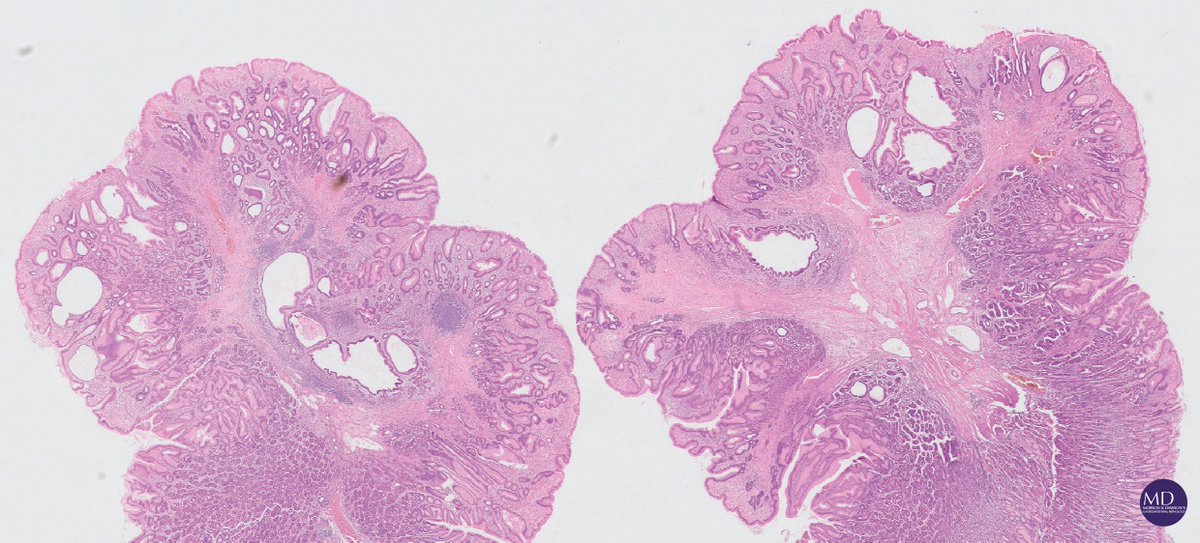

@MD_GIPath

Morson GI pathology

8 years

Clean sweep in a young patient with Cowden's syndrome (PTEN-mutation documented), polyps from all major GI sites reveals the syndrome's phenotypic heterogeneity @DraEosina @RhondaYantiss @abobbyandrews @gordon_hutchins